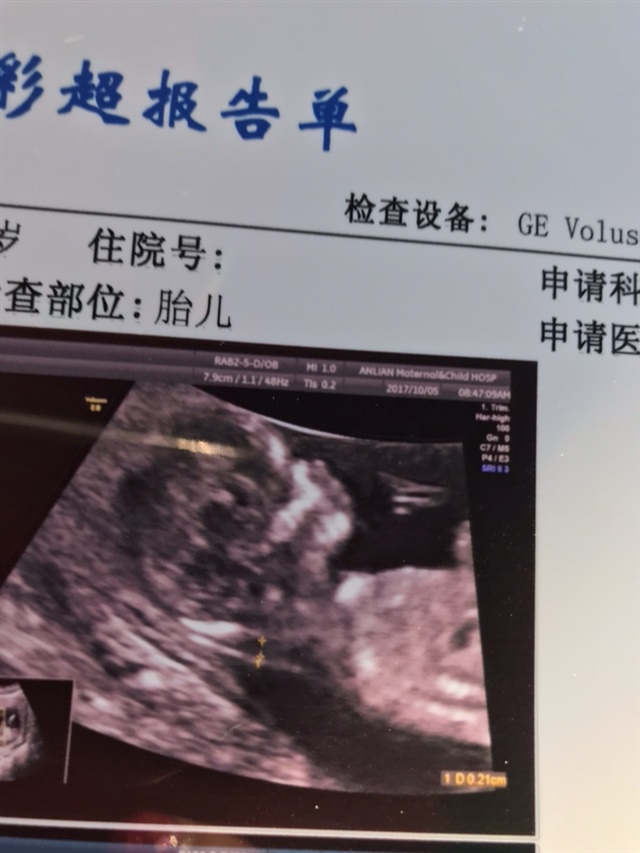

雨翔

孕12周+6天

女孩👧🏻

大琦🐳[帖主]: 怎么看的女孩呢,好多人都说像男孩